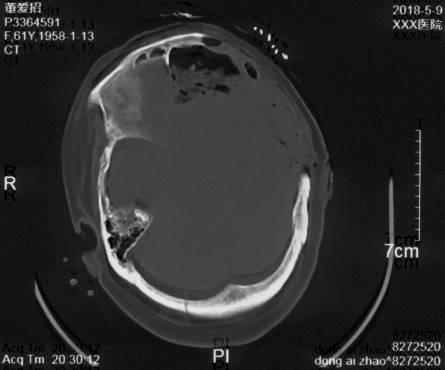

复阅2018年5月9日CT片:左额颞部开颅术后改变,部分颅骨缺如,左颞部脑组织见气体影,双侧额叶及右侧小脑见斑片状高低混杂密度影,大脑镰旁见线状致密阴影,右枕骨骨质断裂。提示左额颞部开颅术后改变,部分颅骨缺如,左颞部脑组织积气,双侧额叶及右侧小脑挫裂伤,蛛网膜下腔出血,右枕骨骨折。

图6-8,2018年5月9日 CT片,左额颞部开颅术后改变,部分颅骨缺如,左颞部脑组织积气,双侧额叶及右侧小脑挫裂伤,蛛网膜下腔出血,右枕骨骨折